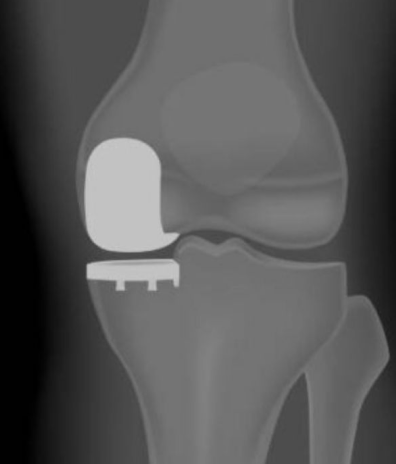

Partial Knee Replacement, also known as Unicompartmental Knee Replacement, is an advanced surgical option for patients with arthritis confined to a single compartment of the knee — either the inner (medial), outer (lateral), or kneecap (patellofemoral) area. With the introduction of Mako Robotic Technology, this procedure has become far more precise, predictable, and patient-specific than ever before.

Mako SmartRobotics™™ is a state-of-the-art robotic arm-assisted system designed to help surgeons perform knee replacement procedures with unparalleled accuracy. Using a 3D CT scan, the Mako system creates a personalized 3D model of your knee, allowing your surgeon to plan the exact size, alignment, and placement of the implant before surgery.

During surgery, the Mako robotic arm helps the surgeon remove only the damaged bone and cartilage with millimeter-level precision, preserving healthy tissue and ligaments.

• Smaller Incision & Less Bone Removal: Only the affected portion of the knee is resurfaced, preserving healthy bone.